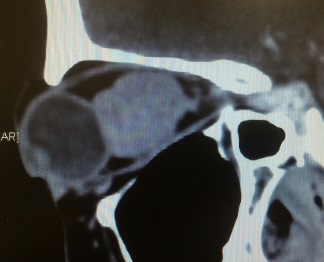

Thyroid Disease

Thyroid eye disease can be as a result of high, normal or low thyroid hormone levels of patients affected with thyroid disease. Depending on the severity of thyroid eye disease, management will be tailored accordingly. Most patients will only require medical treatment but a small proportion will require surgical intervention to correct the appearance and functionality of the eye. In acute cases where medical treatment is refractory, surgical orbital decompression is the only way to salvage a patient's vision. At other times, when thyroid disease has achieved stability, the bulging eye appearance can be alleviated by orbital decompression. Squint from thyroid eye disease can be addressed surgically and eyelid surgery can be performed.